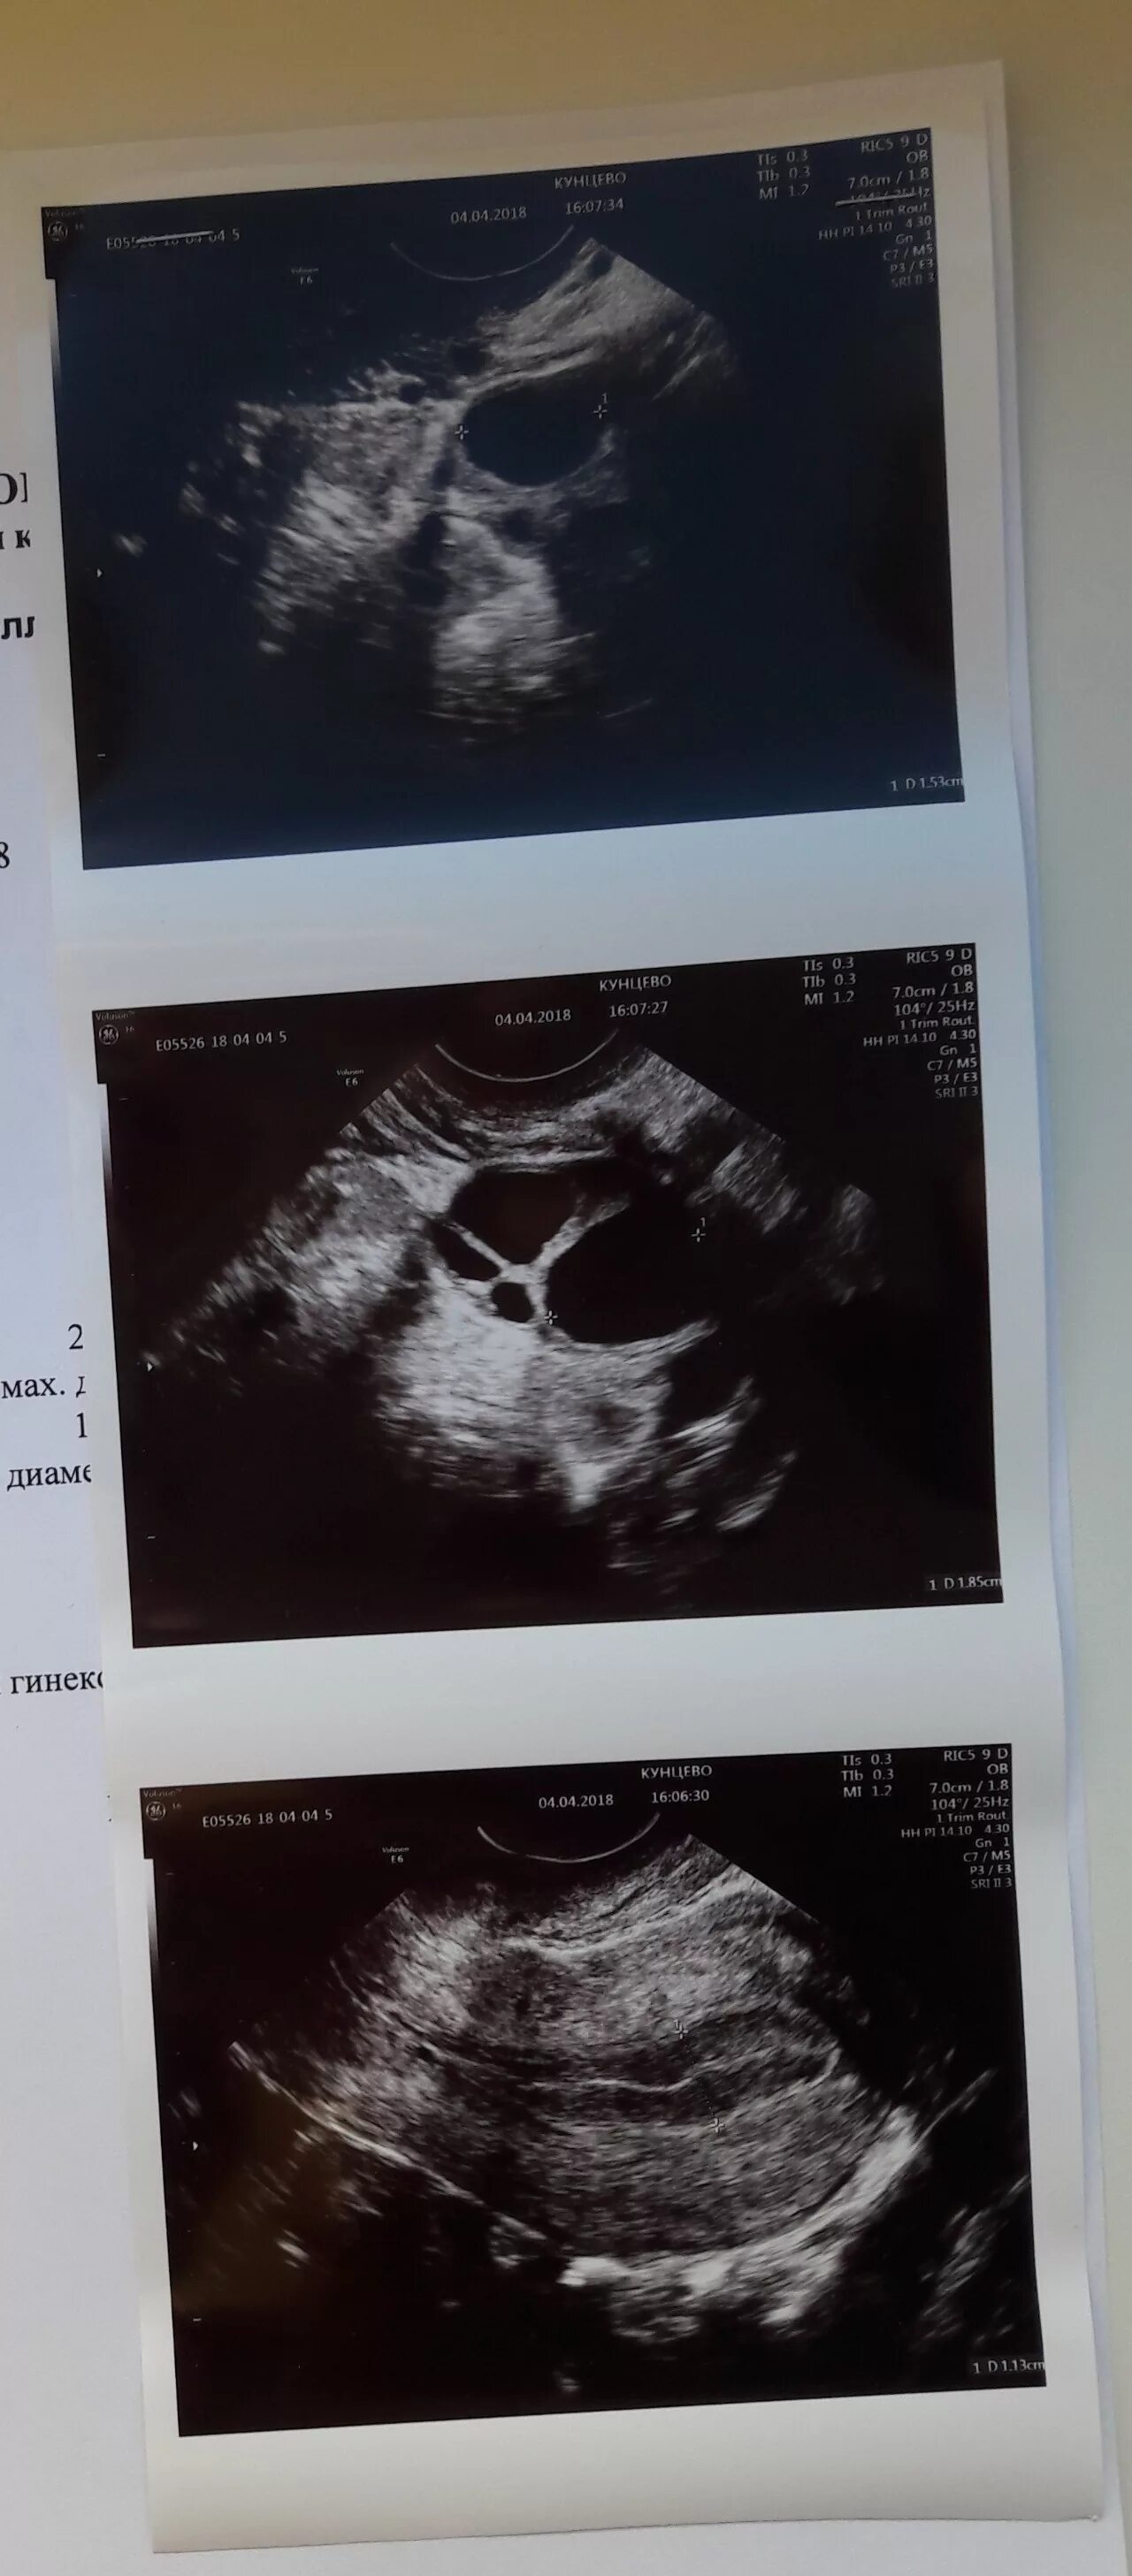

Узи шип